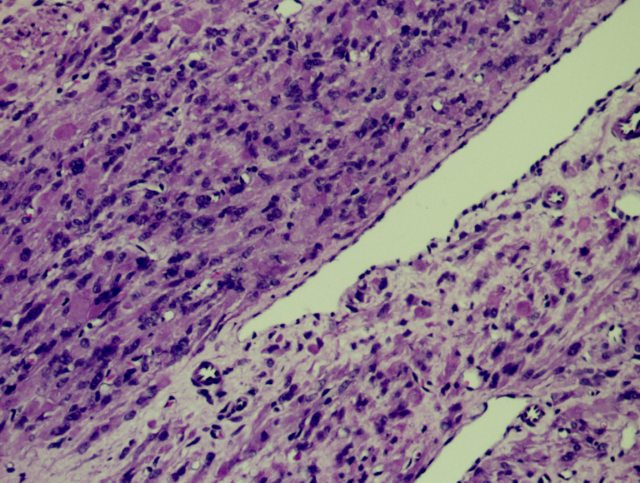

肿瘤细胞密度相对较高,肿瘤间质出现鹿角样血管

肺泡样水肿结构

细胞异型,见多核细胞;嗜酸性核仁,可见胞质内嗜酸性小体

细胞丰富,链状排列的卵圆形核,核异型,见嗜酸性核仁

链状排列的卵圆形核,可见奇异性核;嗜酸性核仁,可见核仁周围空晕

可见胞质内嗜酸性小体

镜下特征:

肿瘤细胞密度相对较高;间质内常出现鹿角样血管;由于间质常伴有水肿,故形成肺泡样水肿结构;散在分布奇异型细胞及多核细胞;细胞核呈卵圆形;细胞核有时出现链状排列;可见胞质内嗜酸性小体;细胞核中可见突出的嗜酸性核仁,且核仁周围可见空晕。

常为轻度的核不典型性,核分裂象<5/10HPF。